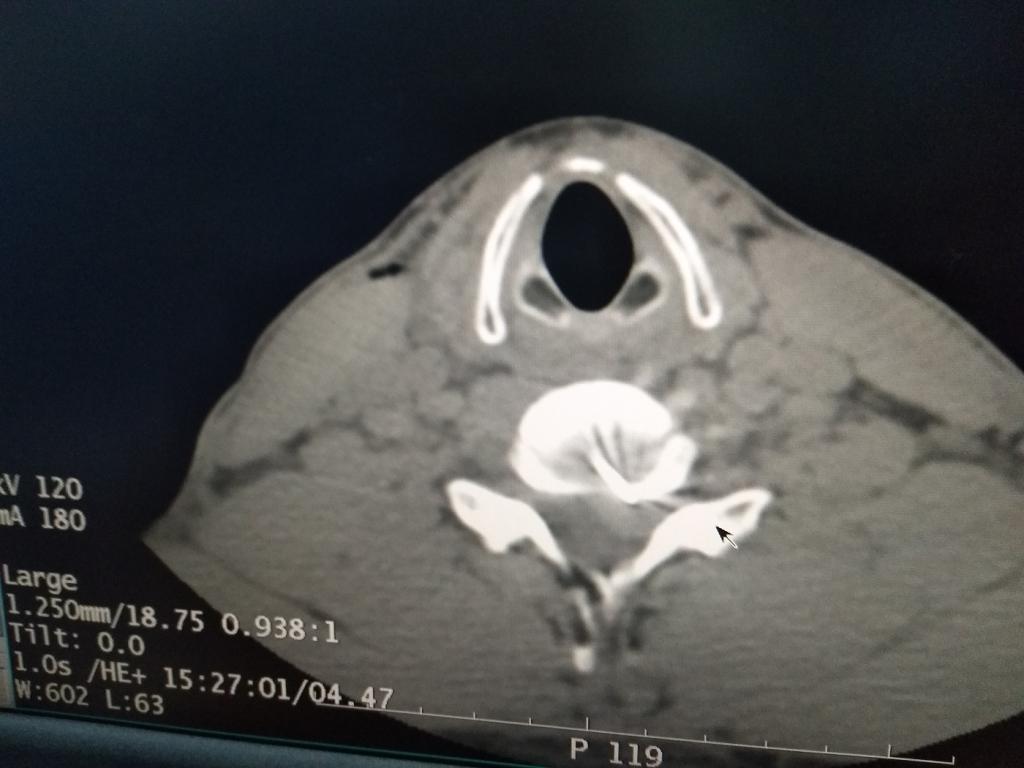

为保证治疗效果,桂林医学院第二附属医院疼痛团队在公主任带领下制定了详细的治疗方案,决定采用颈椎低温等离子椎间盘髓核消融术进行治疗,同时多管齐下:一方面完善影像学、实验室等检查进一步明确诊断;一方面准备手术同时对小李进行脱水、营养神经等,暂时延缓病情进一步发展,并予颈椎旁神经阻滞治疗,改善神经根周围组织循环,减轻水肿。在手术中,公主任团队利用CT测量软件计算出穿刺点和穿刺角度,用B超引导慢慢地将直径为0.5毫米的穿刺针送到突出物内,CT扫描确认针尖位置准确。置入等离子刀头(刀头不过一根针粗细),调整刀头方向,再次确认位置后开始消融手术。整个手术过程约1小时,术后,小李的肩膀和手不那么疼,特别是手指又能拿筷子了。一个月后,小李恢复得很好,肩膀和手不麻也不痛,手也有了力气。